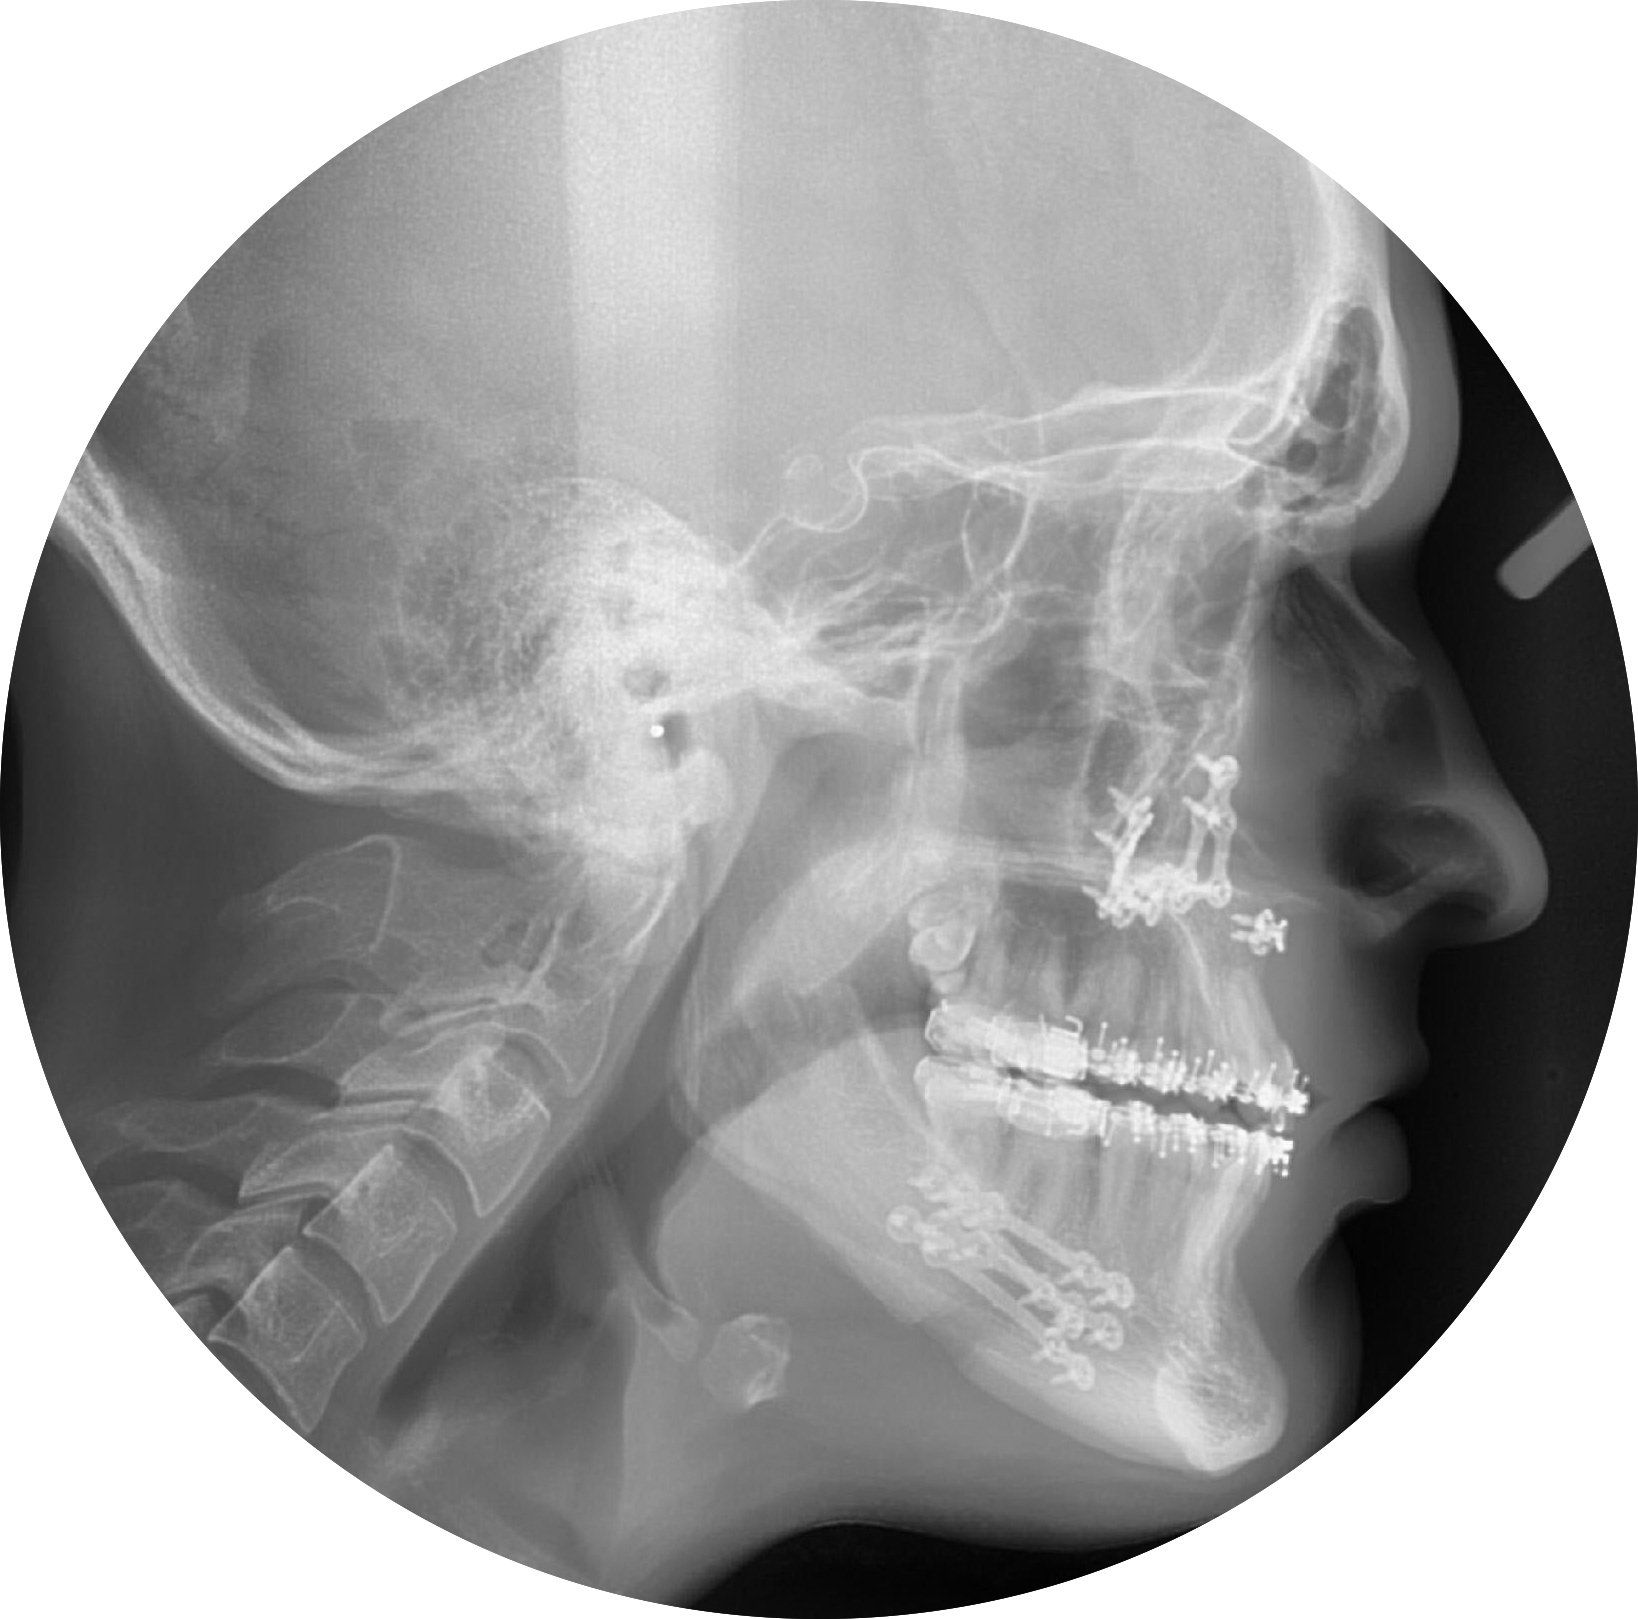

KIEFERORTHOPÄDISCH- CHIRURGISCHE KOMBINATIONSTHERAPIE

Hierbei wird nach Vorbehandlung mit festsitzenden Apparaturen, die Korrektur der Kieferfehlstellung durch einen chirurgischen Eingriff am Ober- und / oder Unterkiefer und kurzem stationärem Aufenthalt erreicht.